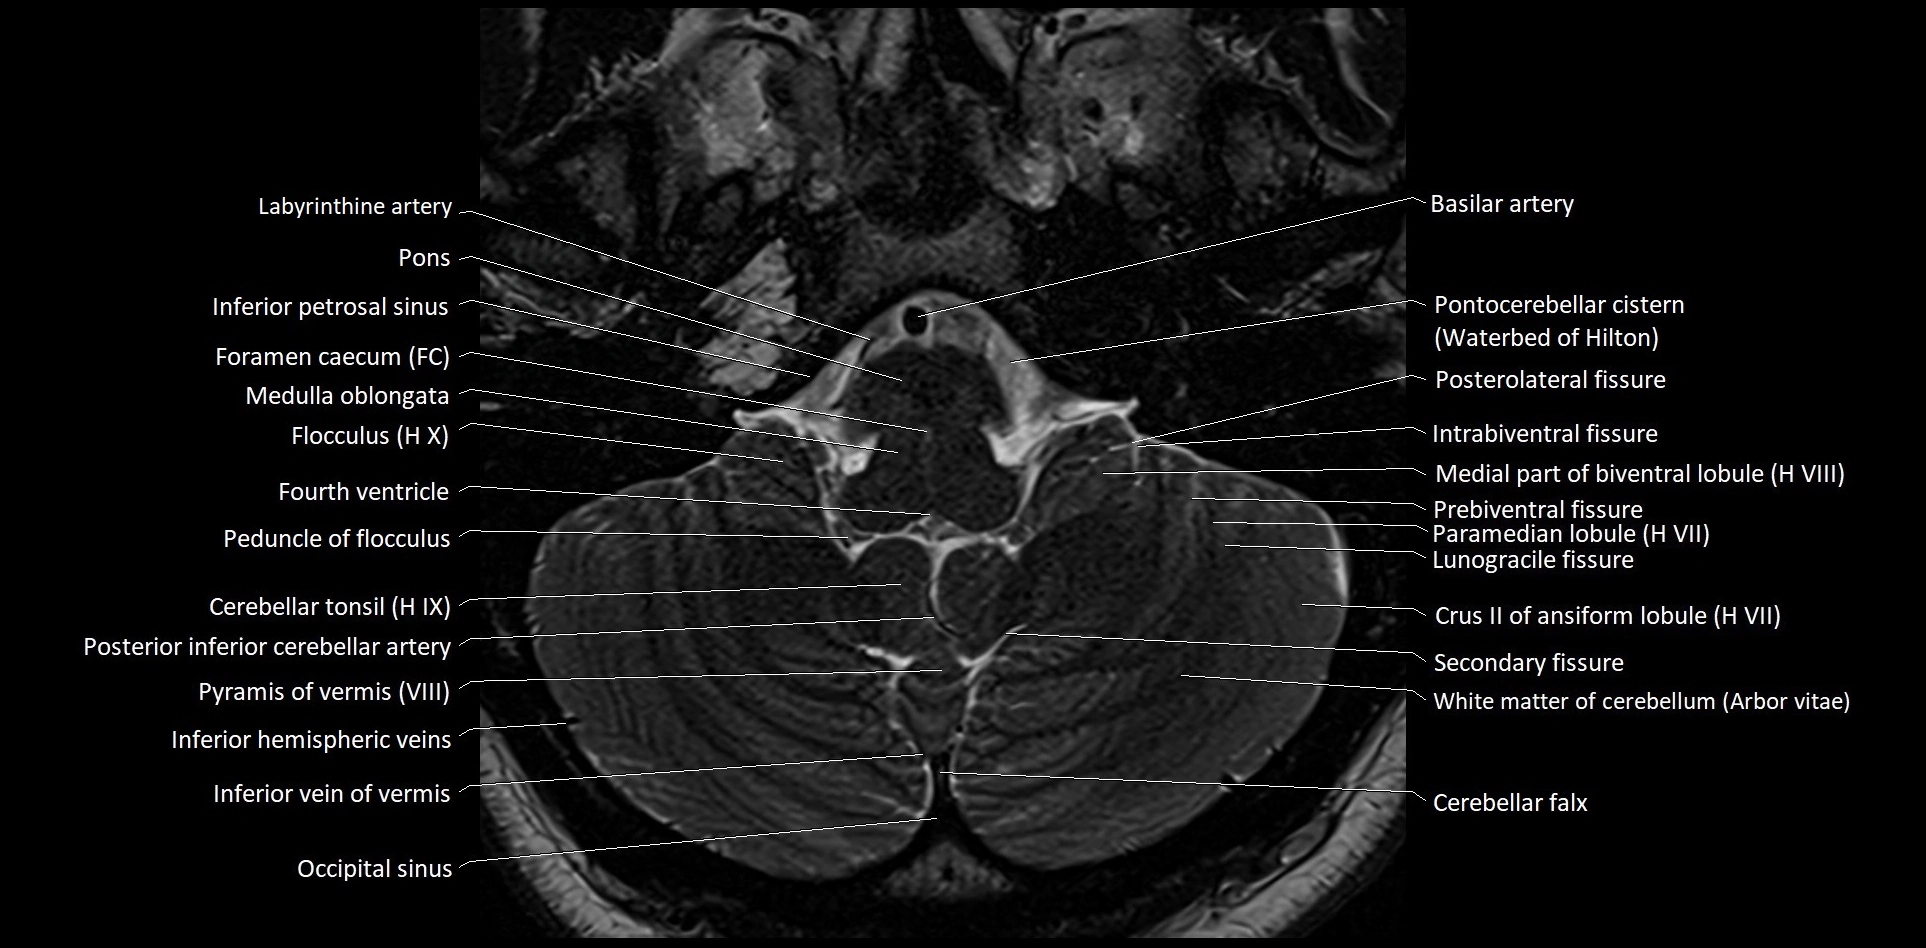

MRI images